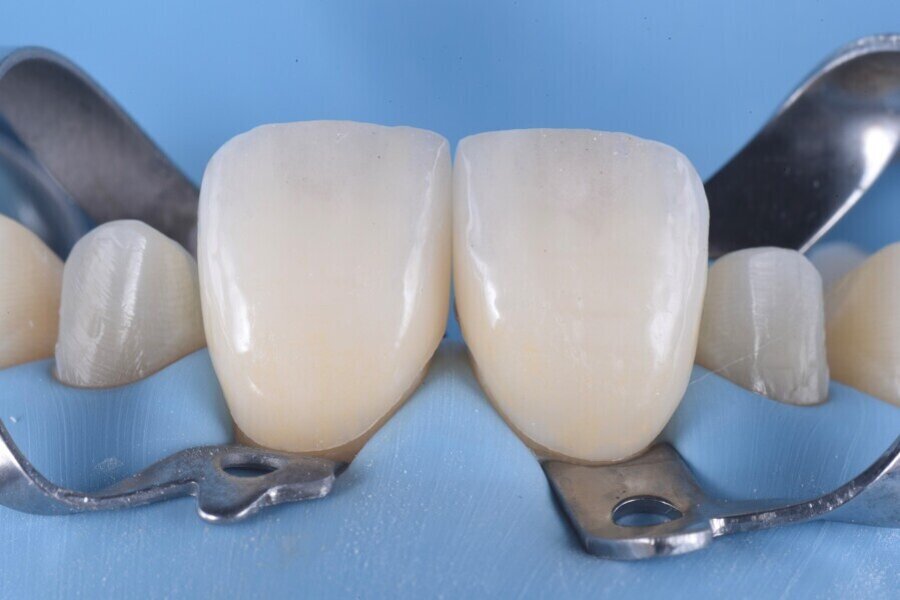

Následně byl zhotoven digitální wax-up ve frontálním úseku horní čelisti, aby bylo možno ověřit estetiku plánované rekonstrukce a vést minimálně invazivní preparaci zubů na základě zhotoveného mock-upu (obr. 8). Finální preparace (obr. 9) se z větší části omezila na interproximální oblasti (obr. 10). Poté byl proveden finální digitální otisk při aplikaci retrakční niti. (obr. 11).

Obr. 11a a b: Digitální otisky předních čelistních korunek.